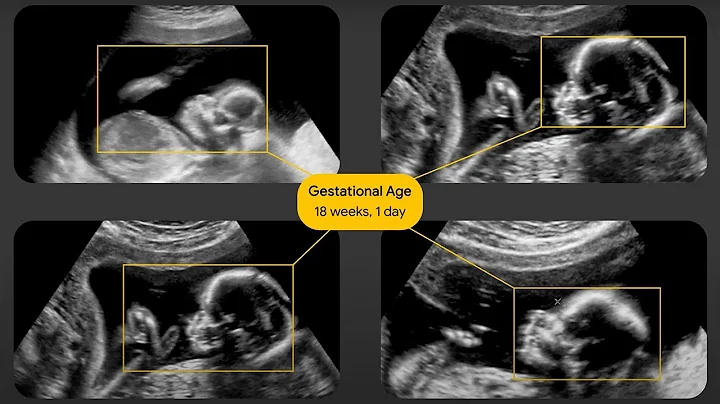

Effortless Ob Ultrasound Scanning: Boost Efficiency With Ai And Automation

Tired of manual measurements slowing you down? Discover how our AI and automation-powered measurement efficiency tools ...